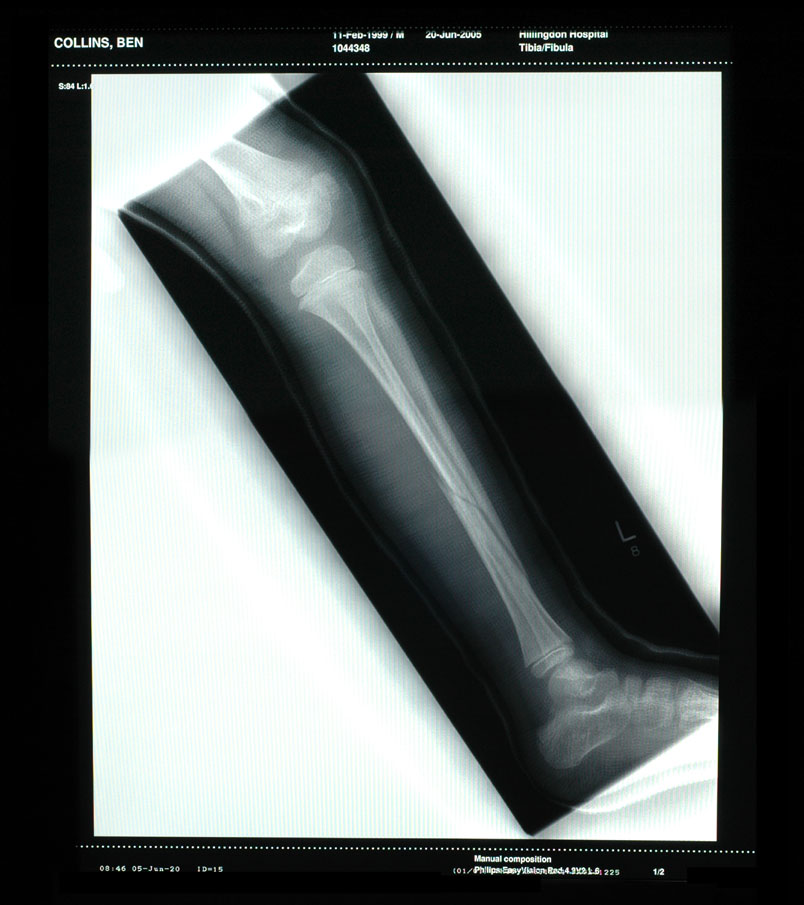

On Sunday, 12th June, Ben broke his leg whilst going down a big 'tube' slide. He was a bit nervous but I said, "What could possibly go wrong..." He's now going around telling everyone that his naughty Dad broke his leg by forcing him down a slide!